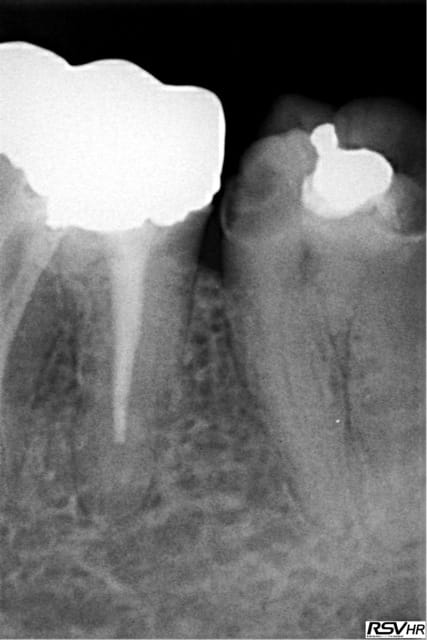

Ah ben moi pas du tout ! ;-) Parce que je ne vois pas le rapport entre être omnipraticien ou exclusif et choisir de faire un traitement moyen juste par "paresse". Parce que vue la radio postop, il y avait largement la possibilité de faire un traitement top niveau. Je ne parle que du manque d"étanchéité qui vient malheureusement ruiner le pronostic du traitement à long terme. Je subodore que les temps d'action des irriguants en fin de préparation mécanique ont été respectés, car là aussi, on peut craindre que trop souvent des traitements radiographiquement corrects voir excellents ne le sont pas autant qu'il n'y paraissent juste par un manque de désinfection chimique.

fouilla t'as oublié de traiter le MV2

@ Marc Apap : je me suis peut être mal exprimé. C'est surtout le manque d'étanchéité en mésial qui m'horrifie dans ce cas clinique. Si il y avait eu 4 parois pendant le traitement et qu'il n'y ait pas de digue, ce serait dommage, mais effectivement pas dramatique si le praticien prenait garde avec son aspi et son assistante. Mais là, en post-opératoire, ce manque d'étanchéité est pour moi forcément dommageable sur le long terme. Il est vrai que si le cocktail bactérien présent n'est pas agressif, ça se passera peut être bien. Ma remarque portait surtout sur le fait qu'au vue de la radio, fouilla avait la compétence et donc la possibilité de faire un traitement top niveau. C'est ce qui s'appelle une occasion manquée.

Je soupçonne moi aussi un MV2 sur la molaire maxillaire... on peut se dire rendez-vous dans dix ans? ;)